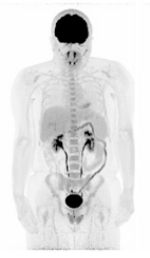

Ultra-low Dose PET Scans Allow Minimal Radiation Burden

Our study demonstrated that high-quality whole-body PET images can be obtained with injected 18F-FDG activities below 10 MBq which result in a radiation burden comparable to a trans-atlantic flight. These ultra-low-dose and CT-less PET protocols could broaden PET applications, particularly in pediatric populations, healthy individuals undergoing screening for cancer, and patients requiring more frequent scans for treatment monitoring.

Sari et al., J Nucl Med. 2025